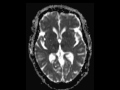

Basilar Tip Thrombosis (top of the basilar syndrome)

This is a 78-year-old female with altered mental status. The axial T2/FLAIR-weighted images demonstre subtle regions of T2 signal prolongation within the bilateral thalami which correspond to acute infarcts on the DWI and ADC maps. The contrast enhanced perfusion maps demonstrate delayed transit within the right and left posterior cerebral artery territories. This case demonstrates top of the basilar syndrome, which occurs when there is thromboembolic occlusion of the distal basilar artery. On clinical examination, the patient may demonstrate visual and occulomotor deficits, behavioral abnormalities, somnolence, hallucinations and dreamlike behavior. Motor symptoms are usually otherwise absent. The differential of bilateral thalamic diffusion restriction includes artery of Percheron infarction, bilateral internal cerebral vein thrombosis, metabolic and infectious causes.